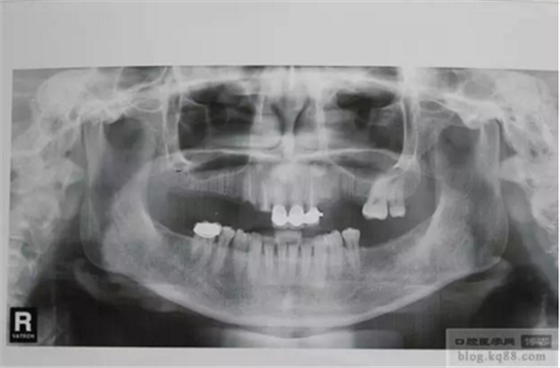

患者:女,40歲,上后牙雙側(cè)缺失多年,左下后牙缺失多年,上前牙多年前做的烤瓷連冠,后牙為支架加球帽附著體,2011年11月上前牙烤瓷脫落基牙齲壞,決定種植牙。

術(shù)前X光片